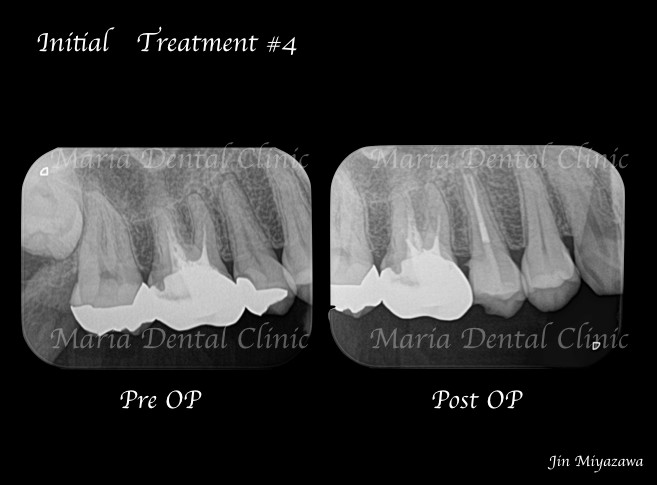

診査の結果、右上5番の歯髄には歯髄生活反応は確認できず、歯髄壊死が起因となる根尖性歯周炎と診断しました。術前のレントゲン診査により、根尖が2つに分岐していることを確認できます。

*赤丸で示しているところは、根が分岐している箇所を示す

今回は右上5番に対しての根管治療における、根尖3mmで分岐する根管へのアプローチでした。